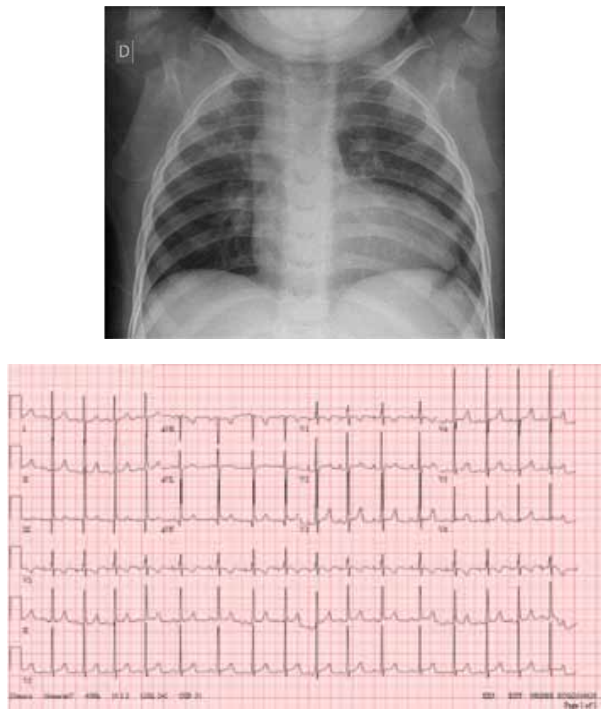

hemodinâmica. Apresenta, a seguir, radiografia de tórax

e eletrocardiograma.

(Arquivo pessoal; imagens usadas com autorização)

Qual é a cardiopatia congênita compatível com essa história e com os exames físico e complementar apresentados?

A radiografia de tórax e o eletrocardiograma, a seguir, de

um lactente de 9 meses referem-se a qual cardiopatia

congênita?